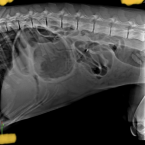

zrejme črevna obštrukcia

(21.07.2023, Adrian, Banovce)

Dobrý den, máme fenku je to cavalier španiel. stala sa taká vec že náš psík začal zvraciať - hnedú tekutinu, následne hlien . nemá stolicu takže si myslím že ide o obštrukciu čriev a gastricidu - neviem či sú zvratky výkali aleb...

Rada od veterinára: MVDr. Barbara Popovičová, VETERAS s.r.o., Košice - okolie, Budimír

Dobrý večer pán Adrian. Veľmi nás mrzí zdravotný stav Vašeho miláčika. Na miernu gastritídu pomáha pol dňová hladovka podávanie vody v malých množstvách následne pár dňová diéta s probiotikami a vhodnou ľahko strávitelnou strav...

Dobrý deň. Ak jej nepomohla predchádzajúca liečba a injekcie vyžiadajte si ďalšie testy a vyšetrenia, krvné vyšetrenia a určite aj sonografiu brucha poprípade RTG . S pozdravom

Dobrý večer, Pri akútnom brušku môžme rozmýšlať nad mnohými diagnózami, napríklad zápal močového mechúra, nálezy na orgánoch ako je pečeň slezina. Je veľmi dôležitá podrobná anamnéza (vek, plemeno pohlavie , či je psík kastrova...